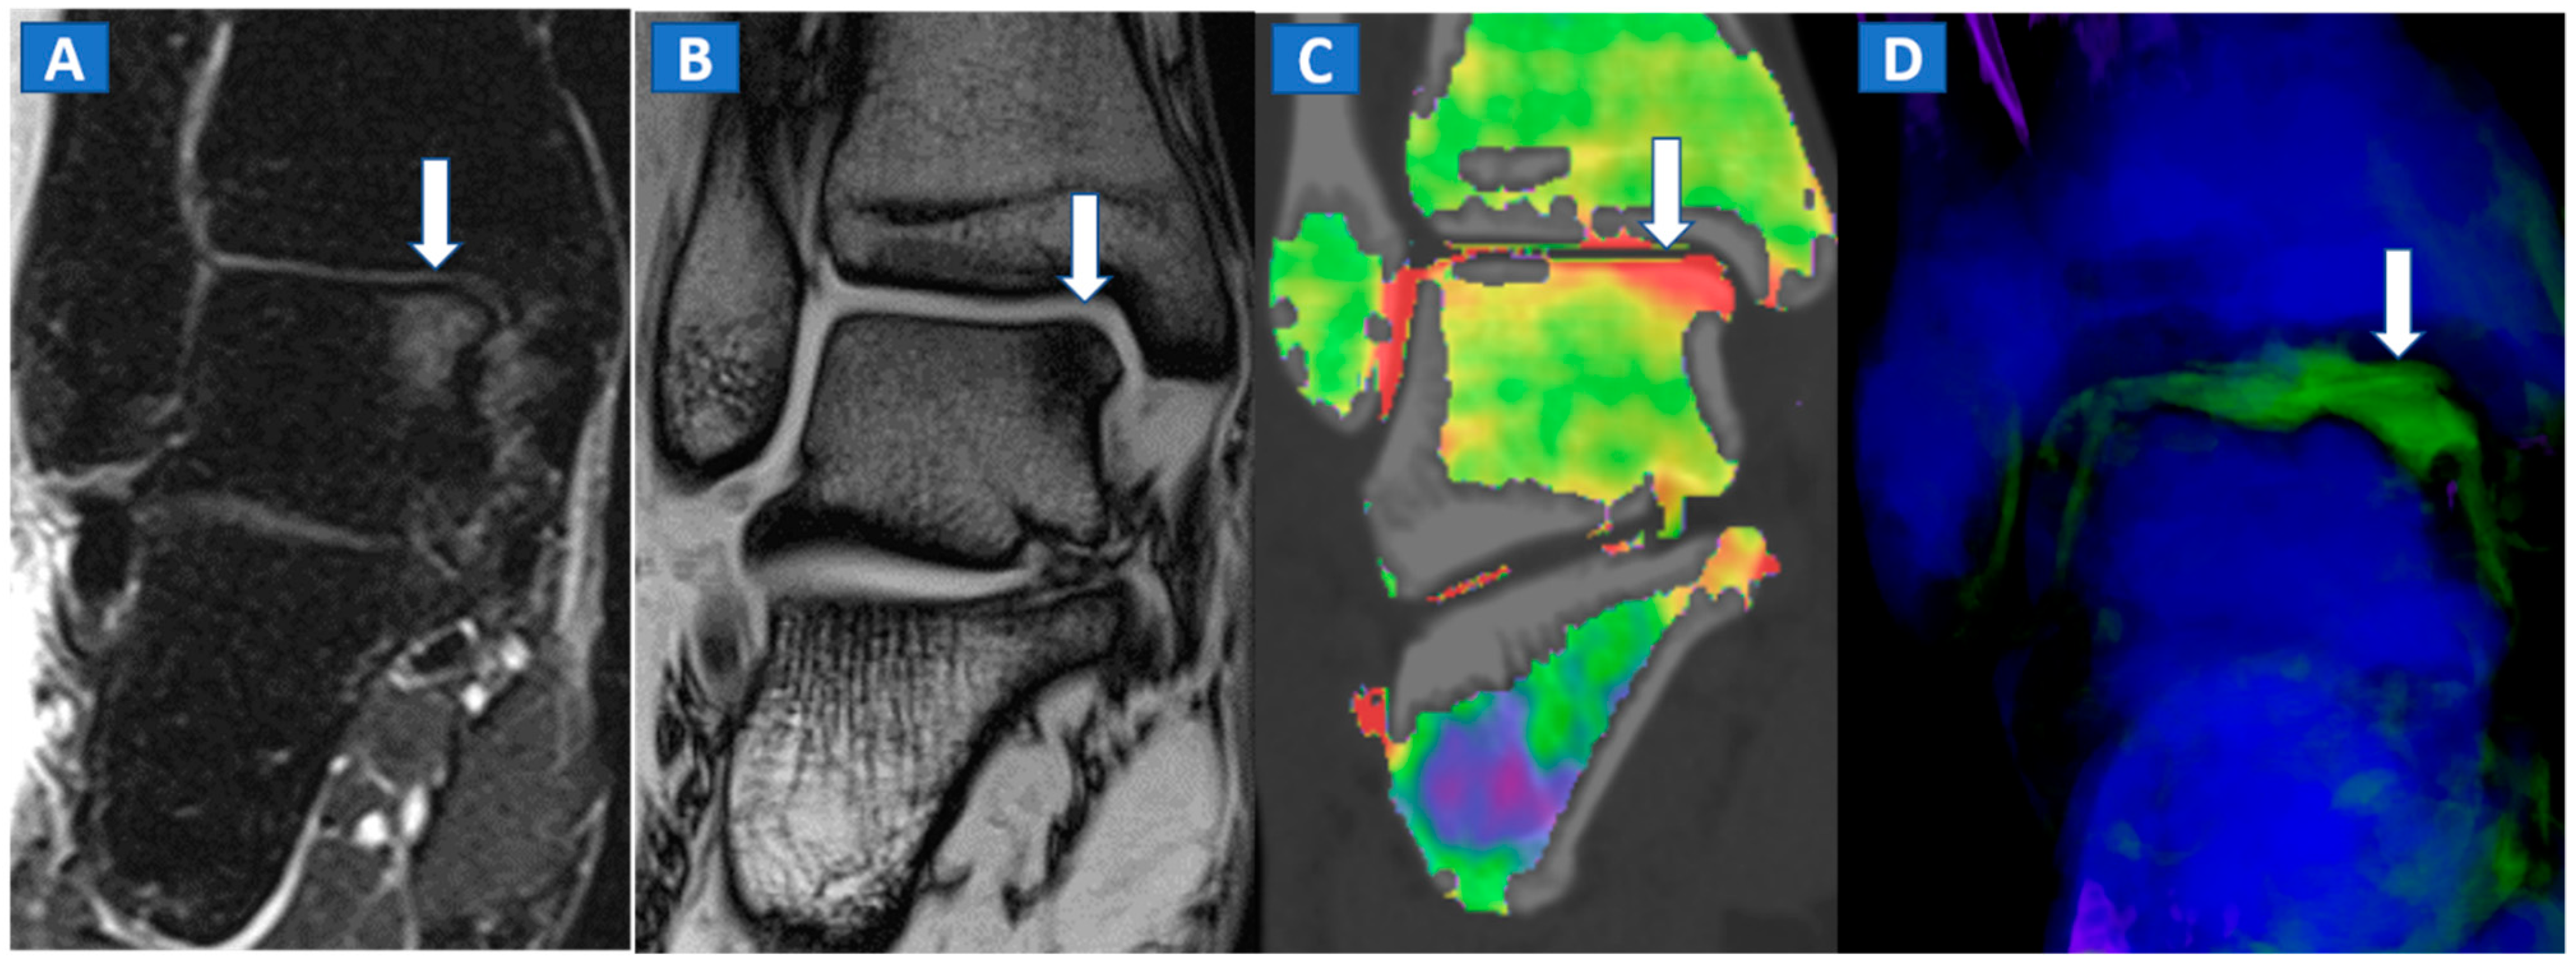

In the post-traumatic shoulder, DECT can identify BME of the humeral head, even in the absence of cortical fractures (Figure 8). Furthermore, in cases of anterior dislocation, CT images can be used for diagnosing Hill-Sachs and bony Bankart lesions.

Figure 8.

A 35-year-old male with traumatic BME of the humeral head. On the coronal STIR MRI image (A), post-traumatic BME of the humeral head is depicted as a hyperintense signal in the subcortical area (arrow). The presence of BME is confirmed on the 2D DECT coronal 1 mm reconstructed image (B) (arrow). The high resolution 1 mm coronal CT image with bone window (C), rules out the presence of cortical fractures.

In evaluating the elbow and wrist, the presence of BME as depicted by DECT, can assist the radiologist in identifying subtle meshed fractures. In addition, the ability of DECT to reduce metal artifacts may facilitate a more reliable evaluation of small anatomical structures, for example in cases of persistent pain after surgery, especially in patients where metallic hardware is present (Figure 9).

Figure 9.

A 45-year-old male with persistent pain after surgical fixation of a middle-third carpal scaphoid fracture. On the coronal T1-weighted (A) and STIR (B) MRI images, metal-induced and motion artifacts impede the correct evaluation of the healing process. Furthermore, subtle BME is depicted proximally (arrow). On the 3D DECT image (C), some proximal BME can be confirmed (arrow). On the 1 mm reconstructed standard CT image on the coronal plane (D), the BME appears as an area of increased density (arrowhead). There are no signs of any residual fractures adjacent to the inserted metallic hardware.